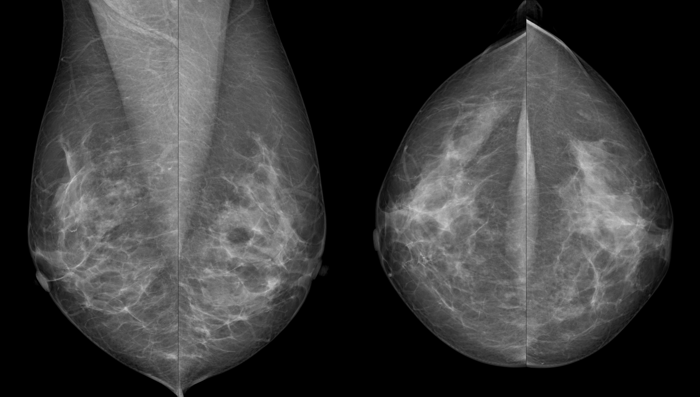

Von jeder Brust werden üblicherweise zwei Aufnahmen - jeweils von oben nach unten (cranio-caudale Aufnahme) und schräg von innen nach außen (medio-laterale oblique Aufnahme) - angefertigt. Die Brust wird dabei in eine Vorrichtung eingespannt und komprimiert:

Die cc-Aufnahme wird immer so dargestellt, dass die Außenseite der Brust im Bild oben liegt.

Wir sehen dieselbe Brust im Abstand von zwei Jahren, die linke Aufnahme ist die neuere. Links erscheint die Brust wesentlich dichter, das Drüsen- und Bindegewebe ist unscharf, die Haut um die Brustwarze ist nur unzureichend abgebildet. Verdächtige Veränderungen könnten eventuell durch die schlechte Bildqualität überdeckt werden. Die Frau hatte an diesem Tag eine sehr druckempfindliche Brust, weshalb keine stärkere Kompression möglich war.

Die Brust ist ein dreidimensionales Organ, die Aufnahmen sind hingegen flach. Um die sichtbaren Strukturen räumlich richtig einordnen zu können, sind daher zwei Aufnahmen in verschiedenen Ebenen notwendig.